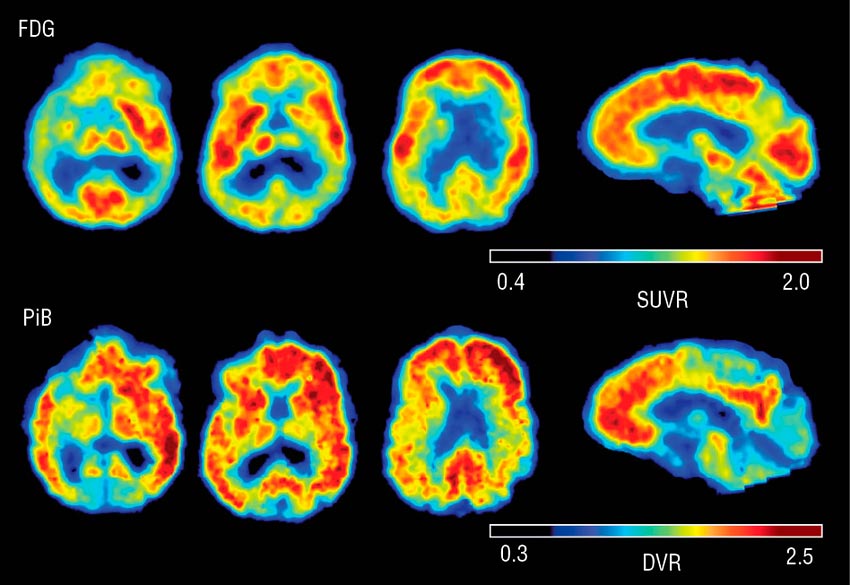

En nuestra experiencia personal,( Cátedra de Ciencias Naturales y su Didáctica 1), la experiencia diaria en el aula ( y en otros espacios durante nuestras salidas y paseos), nos indica que las Neurociencias del Aprendizaje están aportando herramientas que funcionan, ( y mucho). Como ya lo habían descubierto María Montessori y Juan Enrique Pestalozzi en el siglo XIX, cuando ni en sus mejores sueños podrían haber imaginado que algún día se iba a poder observar el cerebro de un niño en el mismo instante en el que aprende. Esto gracias a la PET ( tomografía por emisión de positrones), y a la RMf ( resonancia magnética funcional).

Imagen que acompaña al texto: visualización de las zonas del cerebro activas en el momento de la realización de la PET